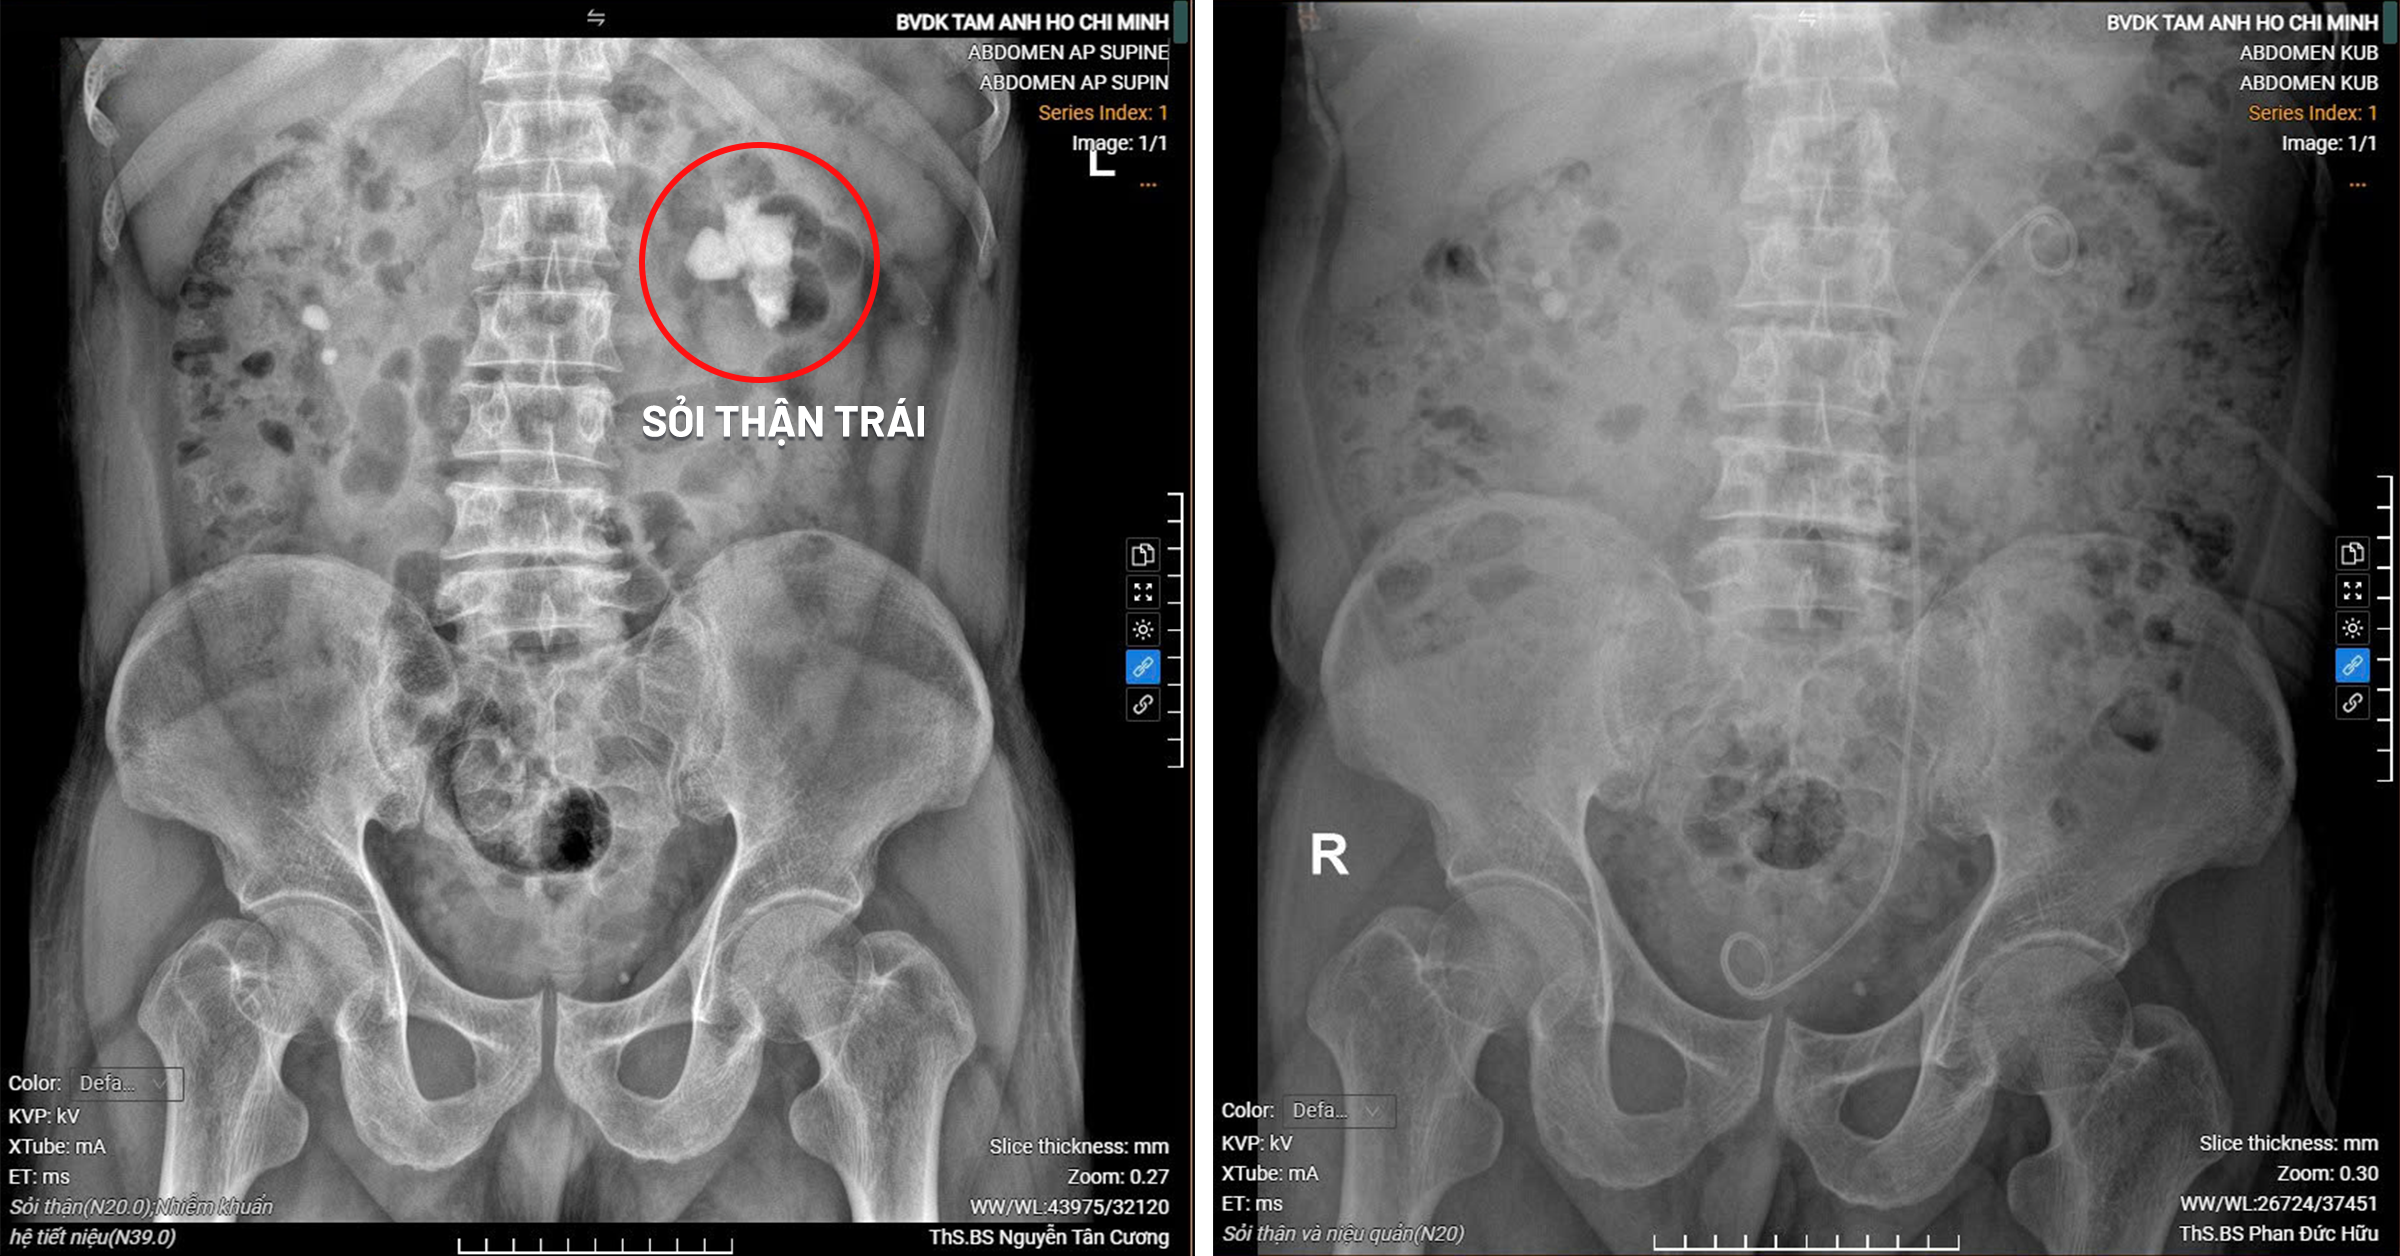

Images of the patient's left kidney with a coral stone before intervention (left) and completely stone-free after intervention (right). Photo: Tam Anh General Hospital |